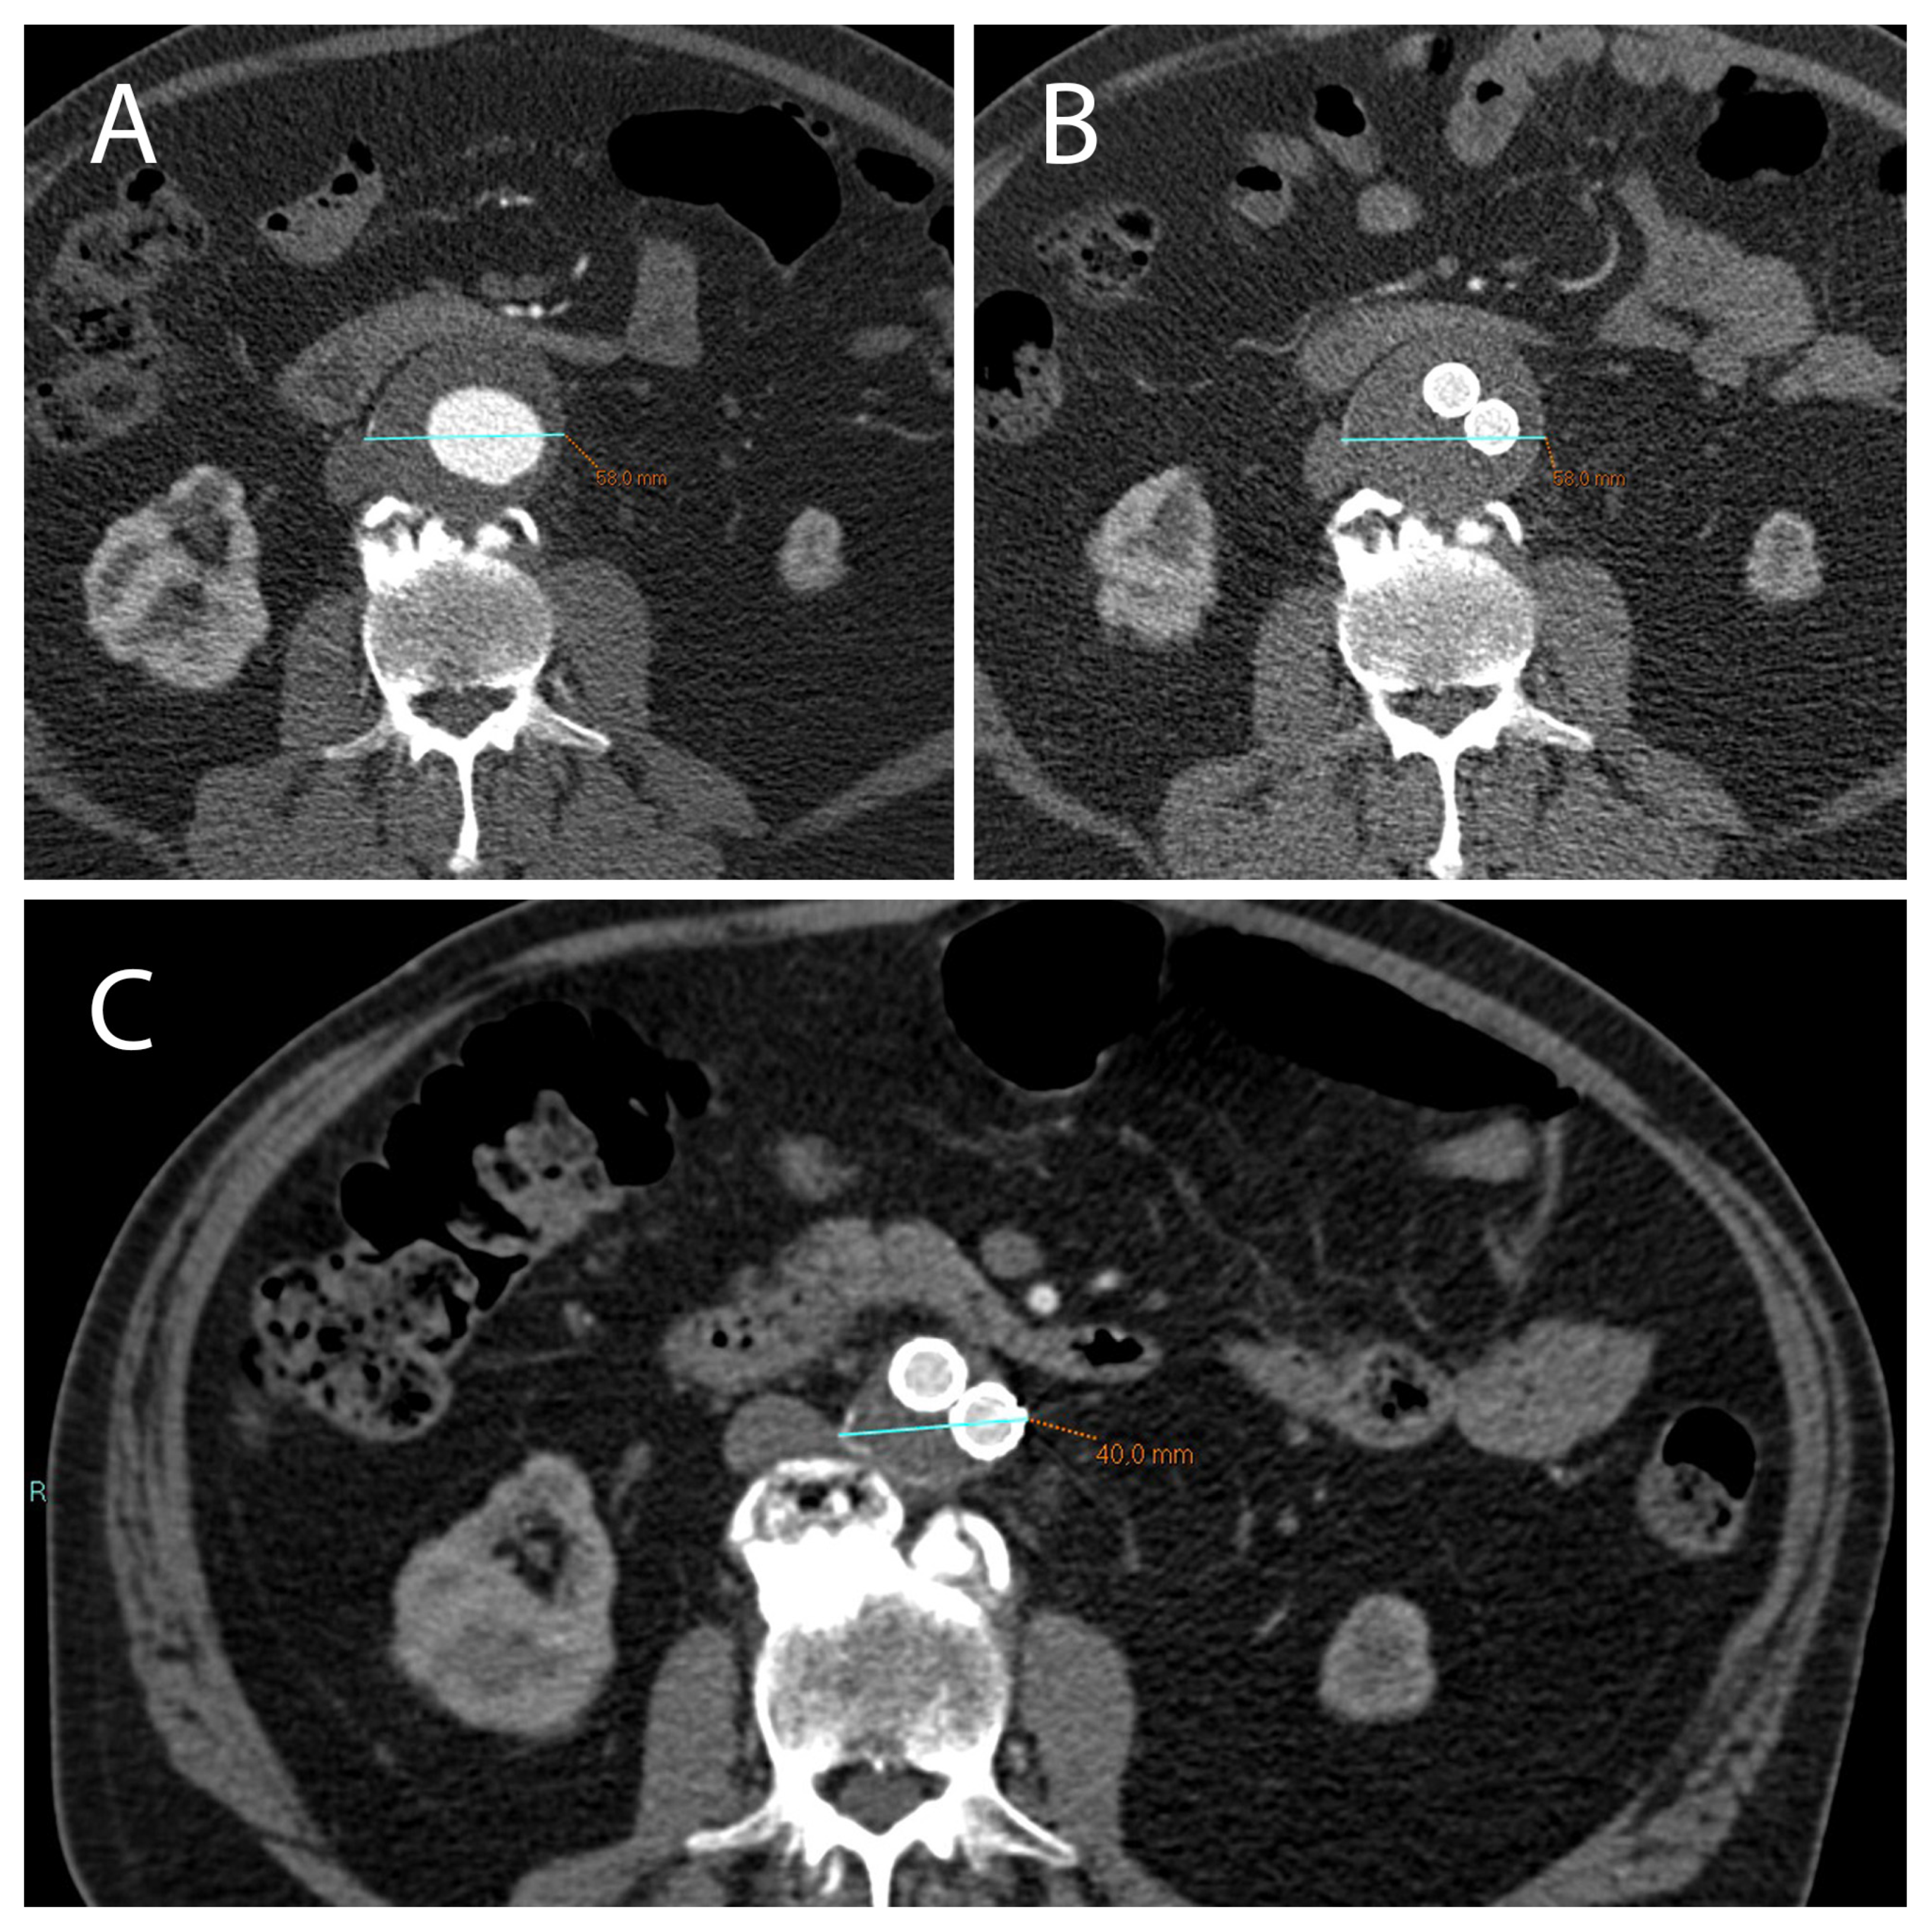

2.1. A Stable Aneurysm Diameter Is Associated with Persistence of Endoleaks